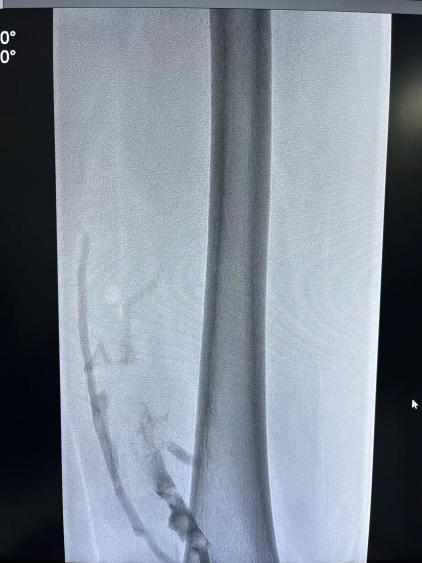

术中造影示:股静脉内大量血栓形成。